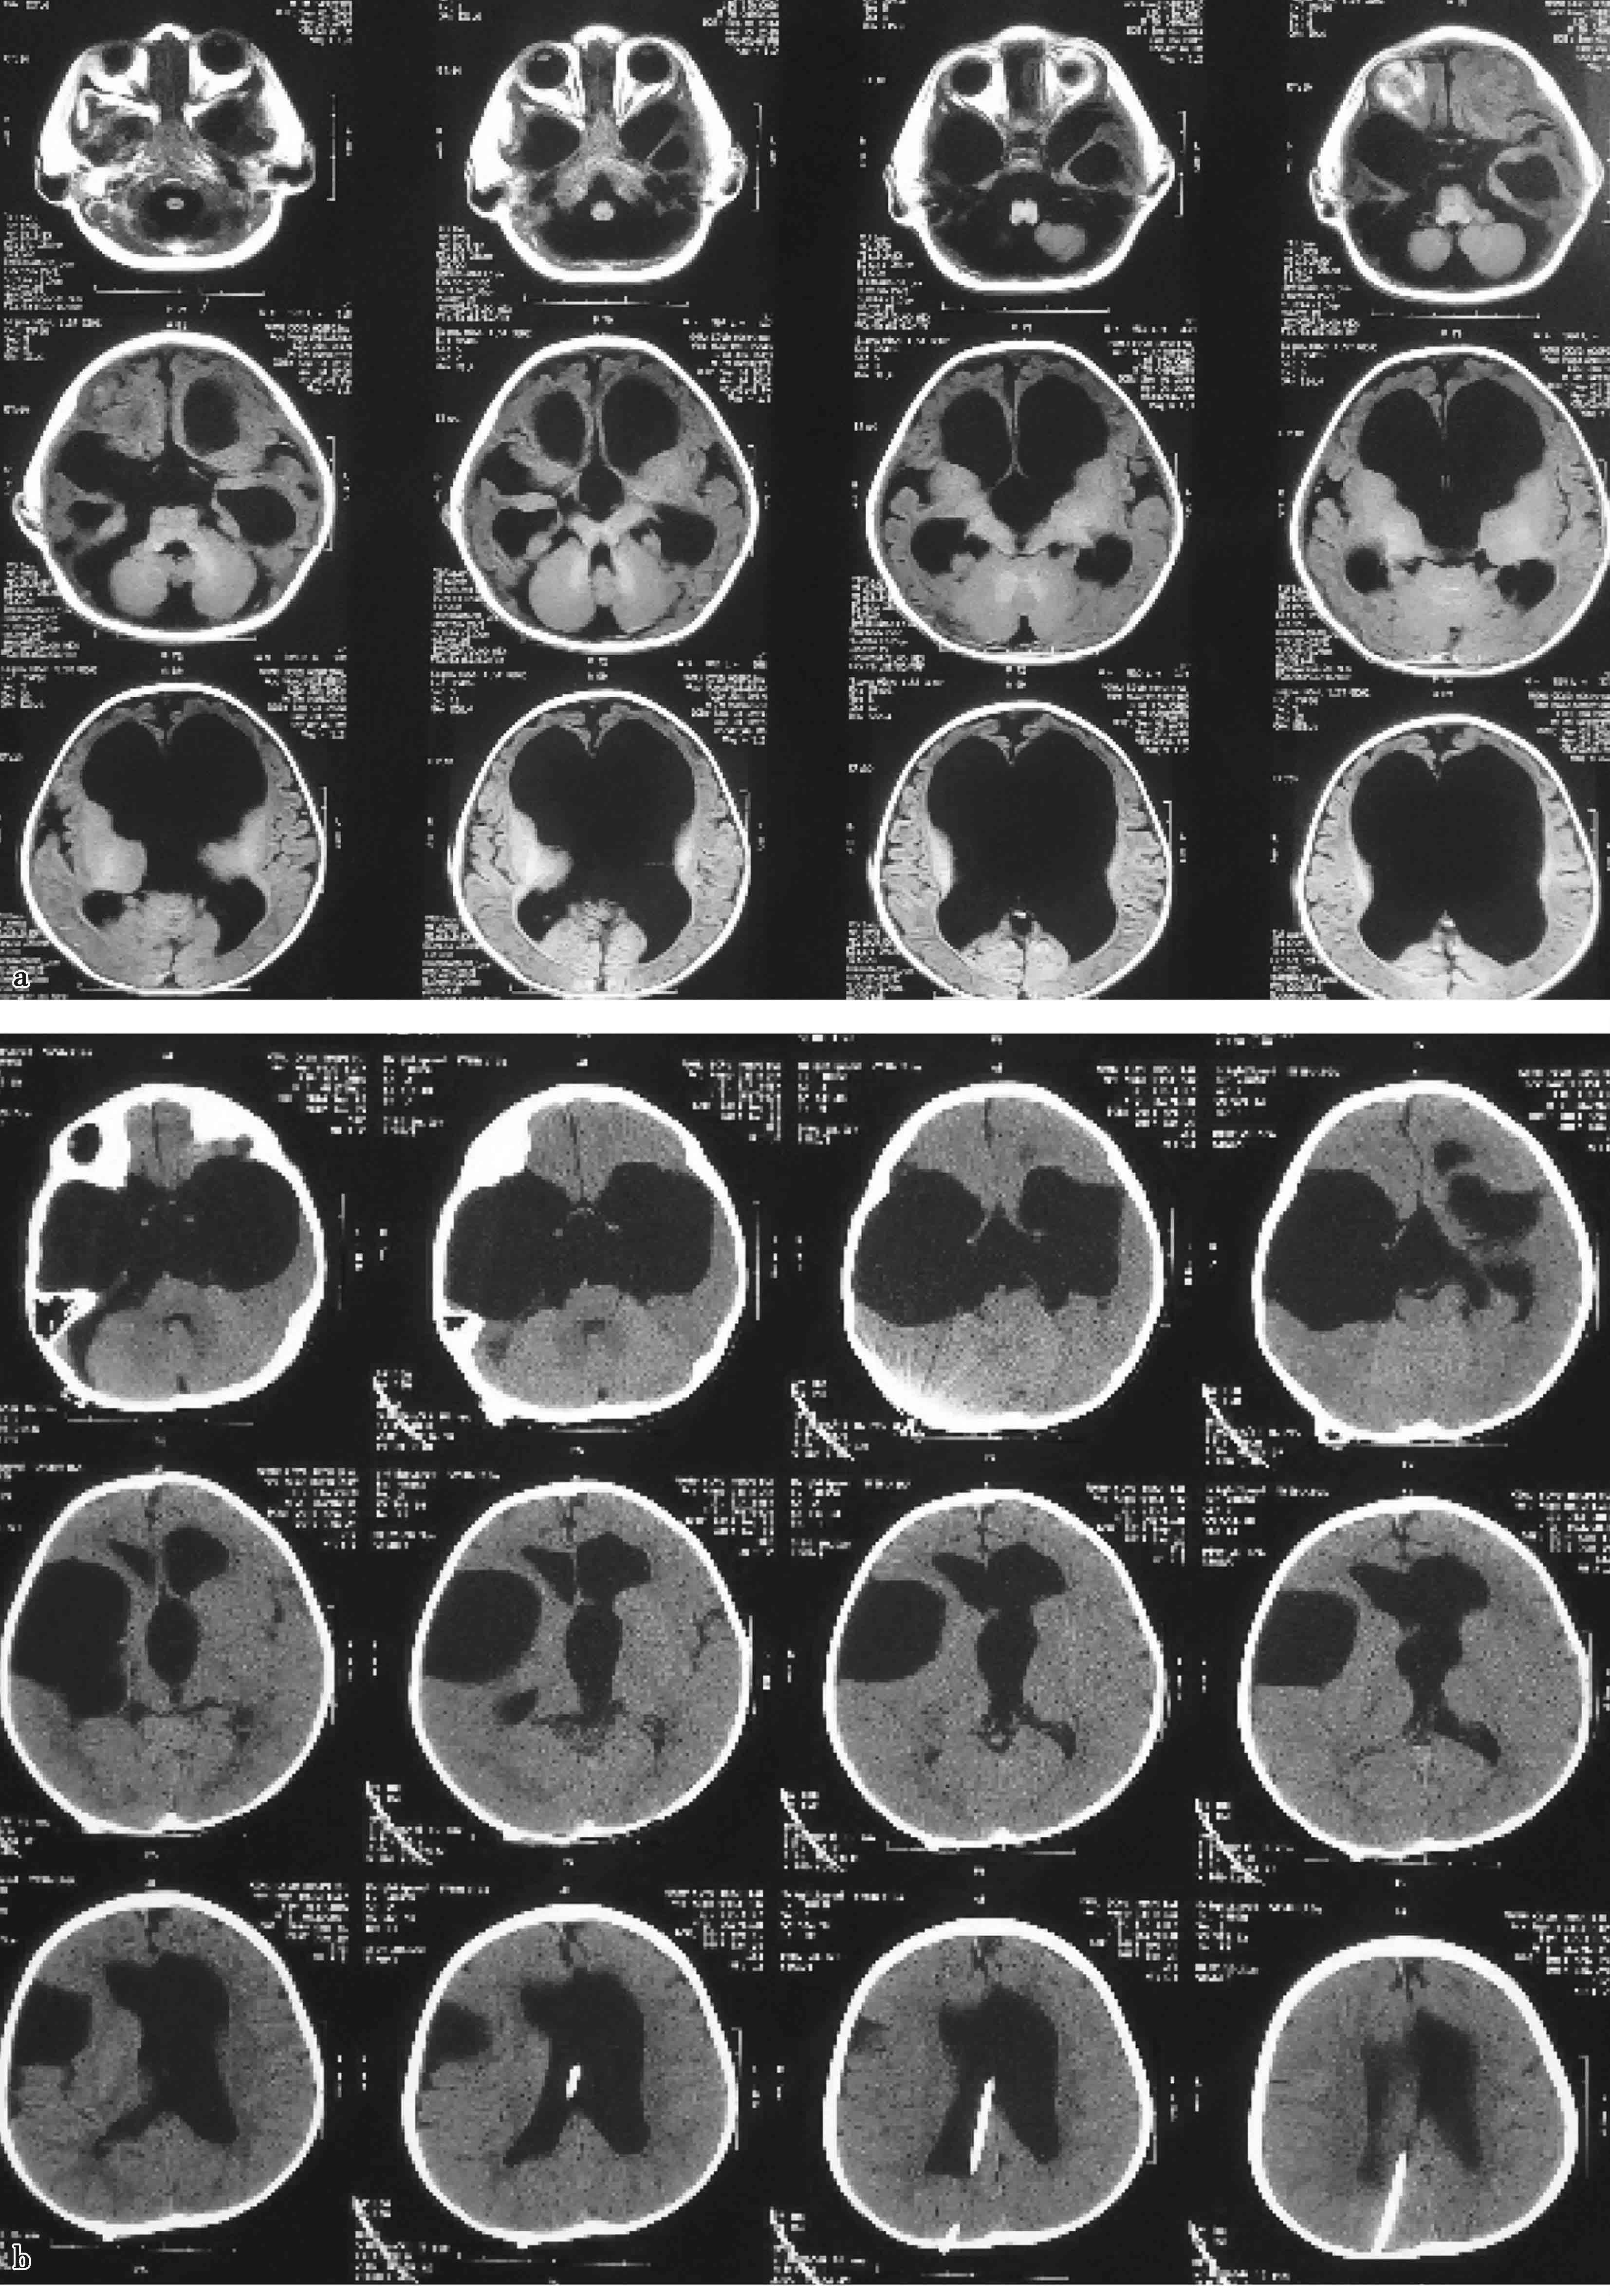

图3-1-1-2 第三脑室底下疝的神经影

a.头颅MRI矢状位片所见,酷似鞍上池囊肿;b.内镜下探查,证实长期脑积水所致第三脑室底深度下疝

图3-1-1-3 内镜下脑室探查,明确导

a.头颅磁共振矢状位片提示导水管梗阻;b.内镜下探查证实导水管内肿瘤

图3-1-1-4 感染后脑积水内镜下探查所见

a.脑室壁上的菌斑;b.脑室内结核所致干酪样坏死物;c.脑室内真菌感染;d.第四脑室内囊虫